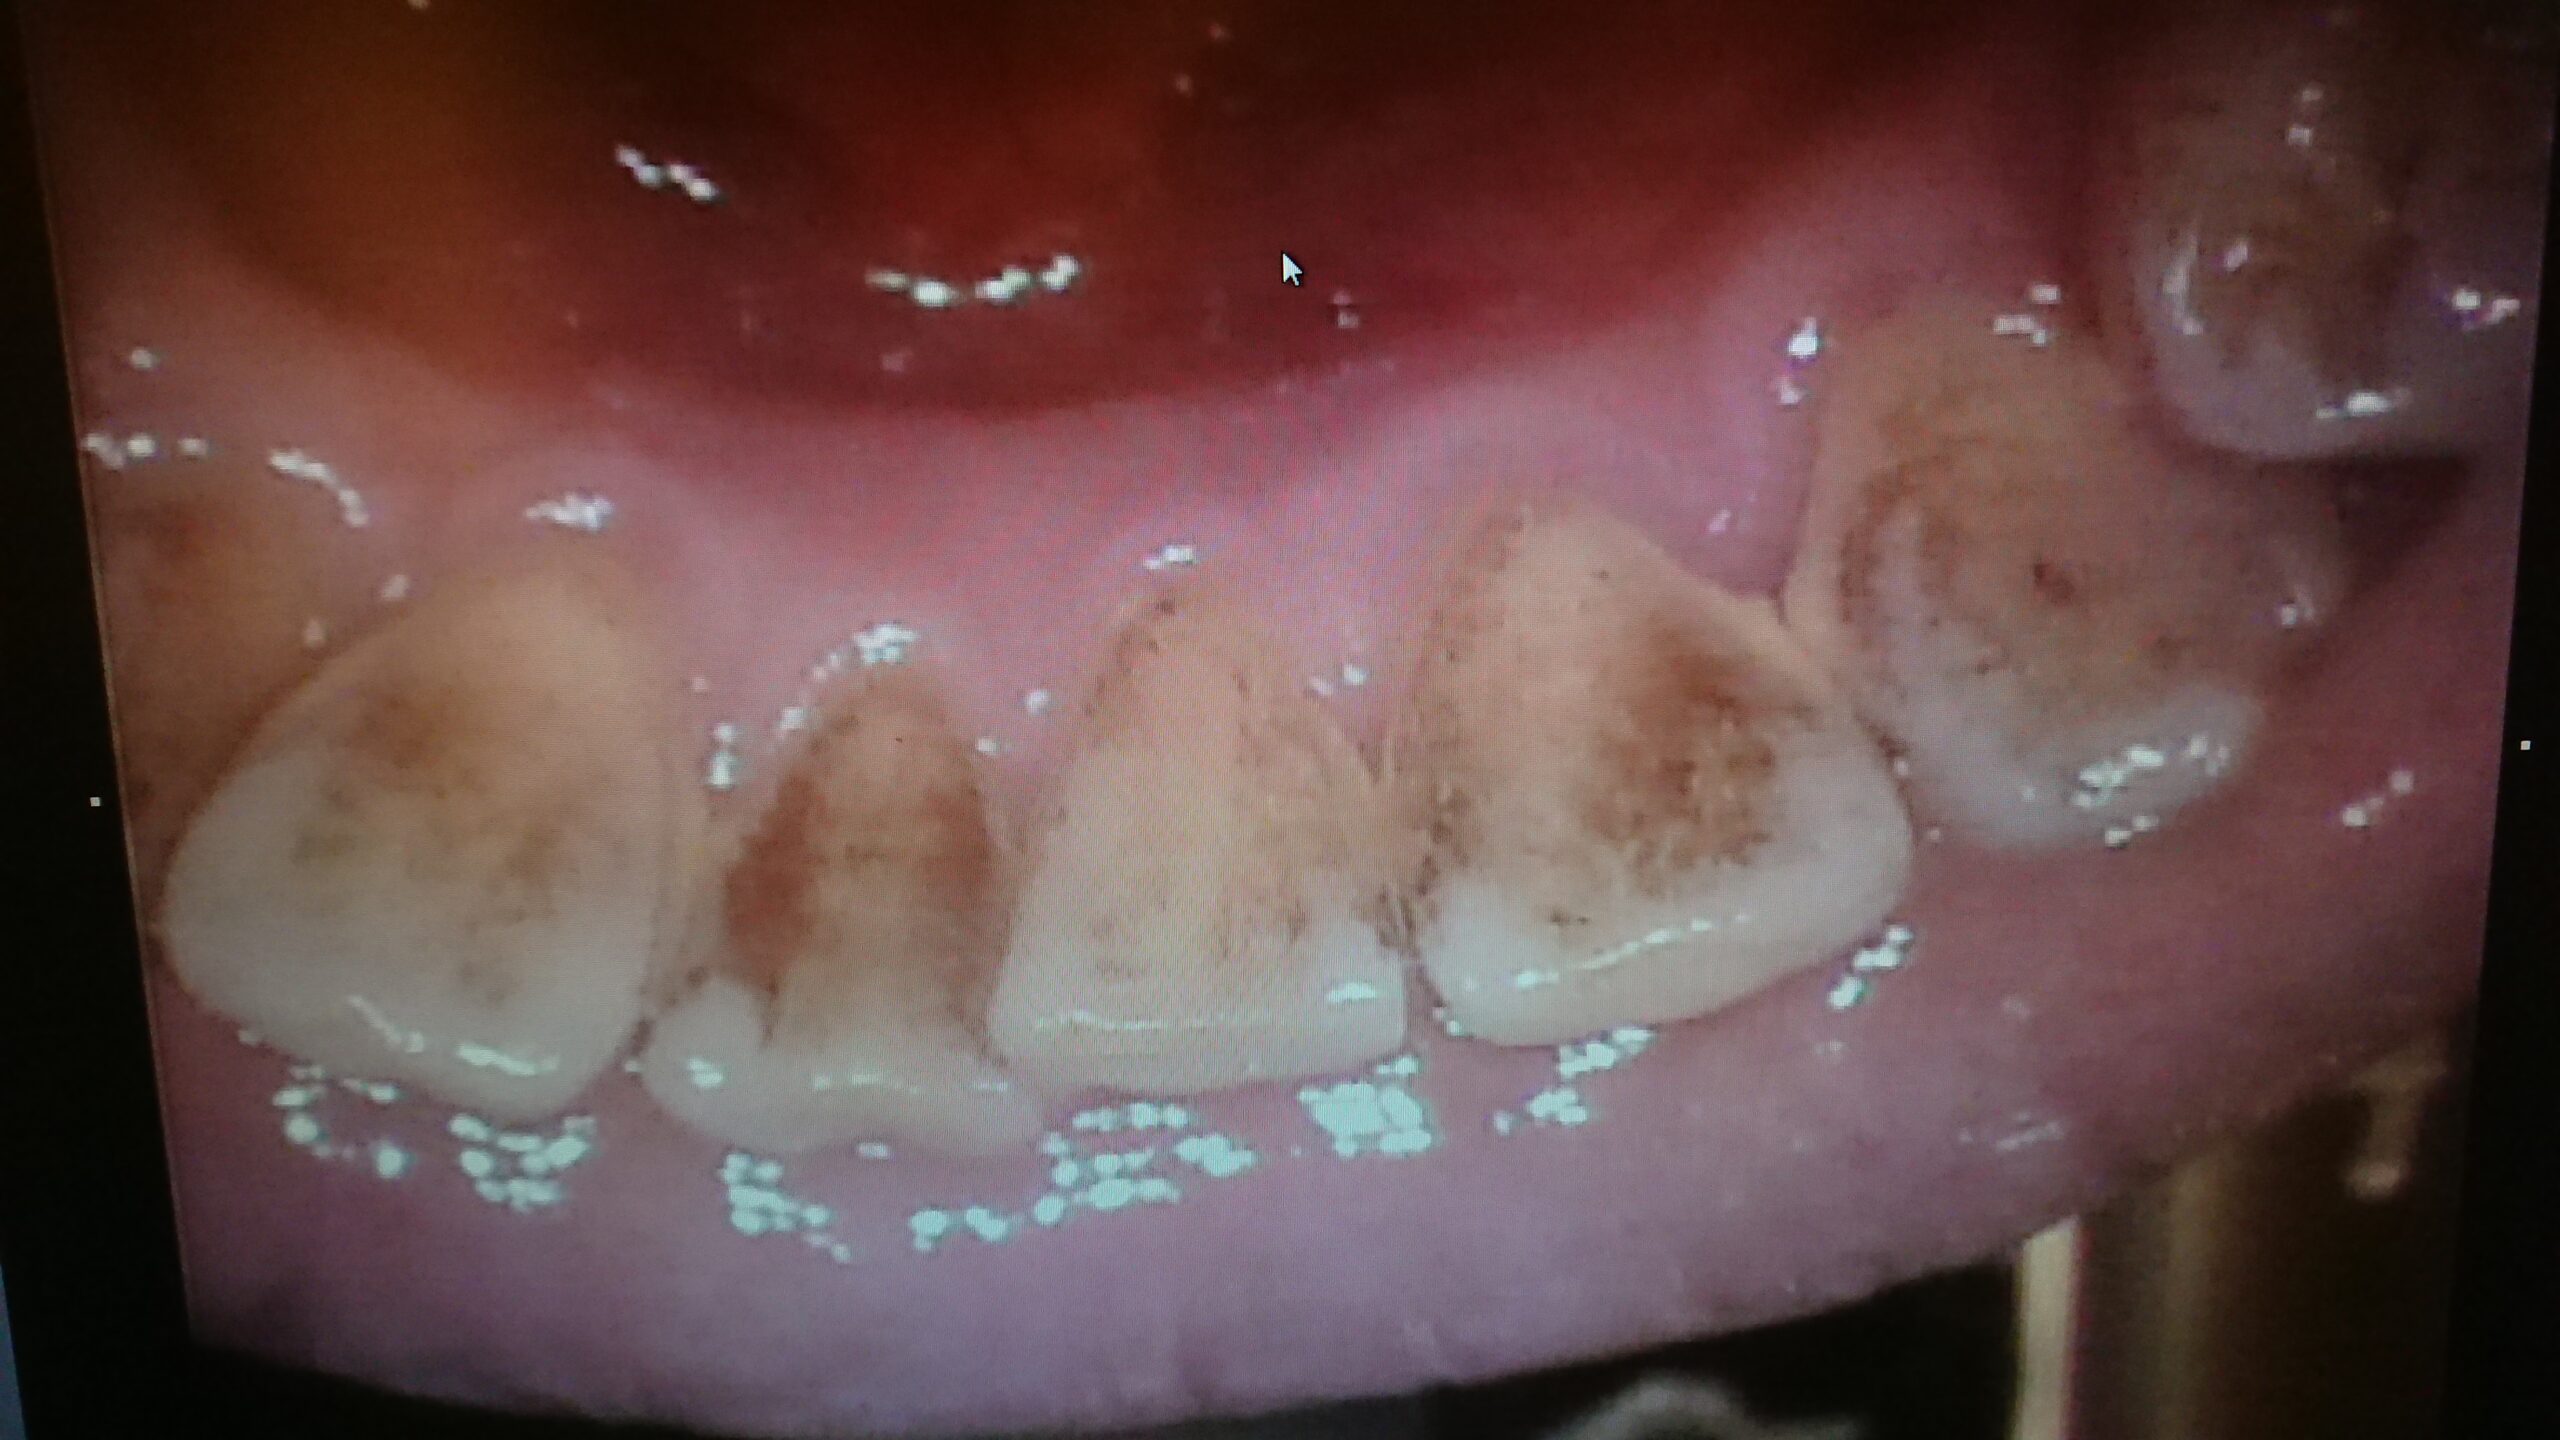

着色の原因

今回は着色の原因についてです✿

(お茶、コーヒー)お茶類に含まれるタンニンは、歯に着色させやすく、一旦着色すると歯磨きではなかなか落ちません。コーヒーに含まれるカフェインは、歯を覆う被膜を着色させ、黄ばみの原因になります。

(タバコ)タバコのヤニは一度つくと歯医者でも落とすのが大変な為何回か通っていただき、クリーニングになる場合があります。